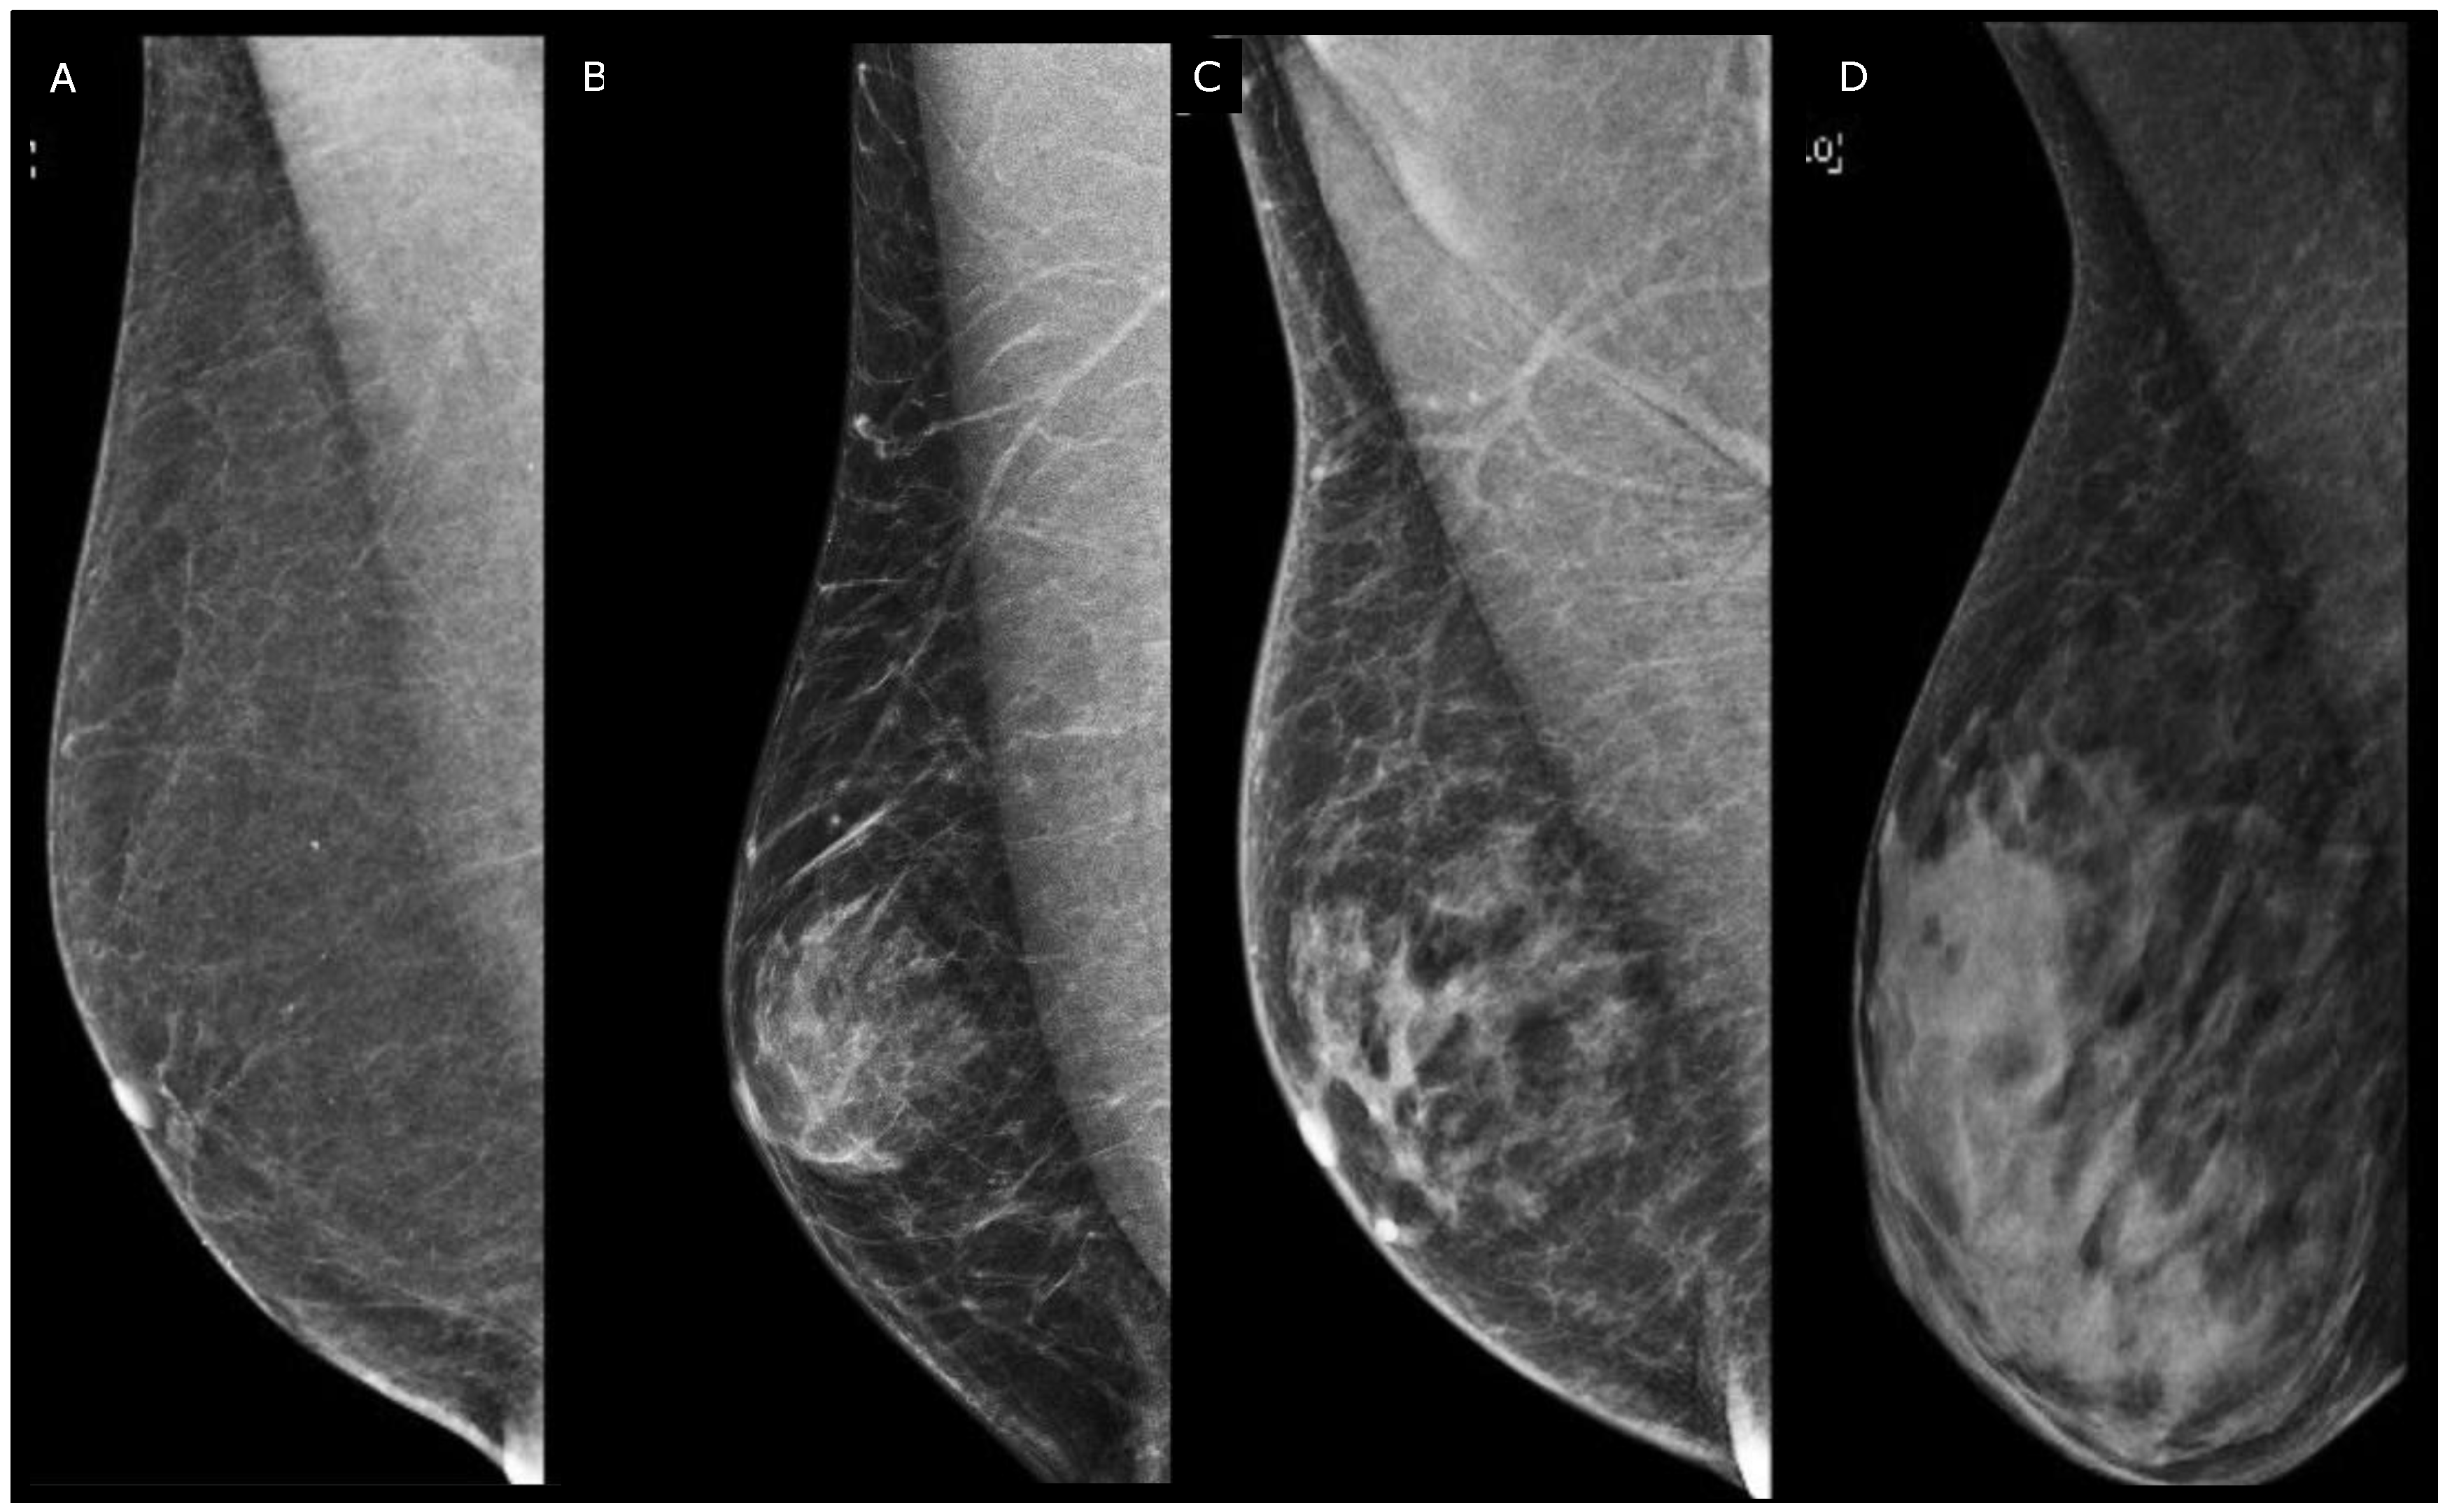

“Transgender” is a comprehensive umbrella term that refers to individuals whose gender identity (their internal perception of gender) and/or gender expression (their outward presentation of gender identity) deviate from the sex assigned to them at birth [46]. Male-to-female (MTF) transition refers to the process in which an individual assigned male at birth undergoes various changes, both social and medical, to align their gender identity with that of a female. Female-to-male (FTM) is the opposite. Transition MTF (Figure 9) may include steps such as feminizing hormone therapy (estrogen with an adjunctive antiandrogen medication (e.g., spironolactone) to suppress endogenous testosterone) to induce physical changes like breast development, as well as gender-affirming surgeries such as breast augmentation and facial feminization surgery or gender confirmation surgery (commonly known as sex reassignment surgery) [47]. The transition FTM can include the gender-affirming surgery top surgery with removal of breast tissue, orchiectomy, hysterectomy with bilateral salpingo-oophorectomy, facial feminization surgery, chondrolaryngoplasty, and gender-affirming hormone therapy: testosterone (by IM injection or by transdermal patch, gel, or implant) [47].

Figure 9.

Mammography in cranio-caudal (A) and medio-lateral oblique (B) views in a 52-year-old transgender woman after 5 years of hormone therapy.